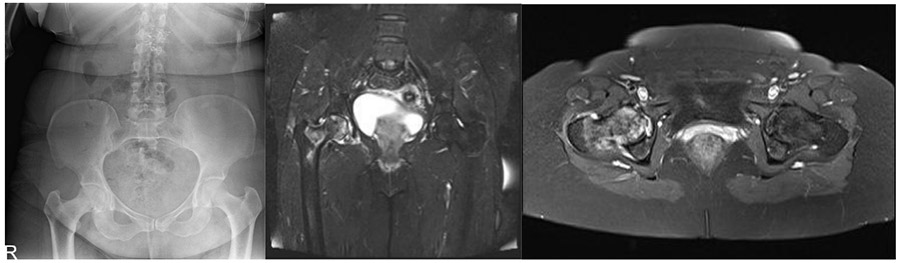

CASE 24: Breast cancer metastasis to the hip (femur head and neck)

Before the surgery: X-ray shows irregularity and increased density in the head-neck space of the right femur, and MRI shows involvement, damage, and increased fluid in the joint at the head-neck level of the right femur.